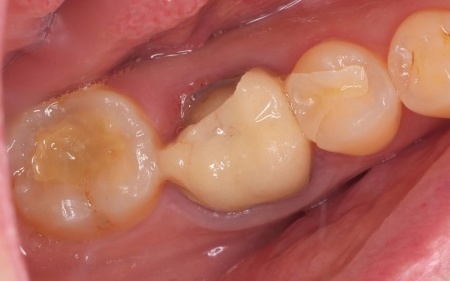

| 診断 | 拝見したところ、右下奥歯に装着されていた被せ物が、経年劣化による強度の低下で大きく破折していました。

このまま放置すると、奥歯でしっかり噛むことができないだけでなく、欠けた被せ物で舌が傷つくおそれがあります。 |

| 行ったご提案・治療内容 | 欠けた被せ物は10年以上前に治療した部位とのことで、材質はセラミックの一種であるポーセレンだと考えられます。 再び破折する危険性を考慮して、セラミックの中でも人工ダイヤモンドと呼ばれるほど高い強度をもつ「ジルコニア」での修復を提案し、同意いただきました。 メリット デメリット まずは右下奥歯の古い被せ物を除去し、歯の形を丁寧に整えます。 後日、完成した被せ物を装着し、見た目や噛み合わせに問題がないことを確認して、治療を終了しています。 |

治療前